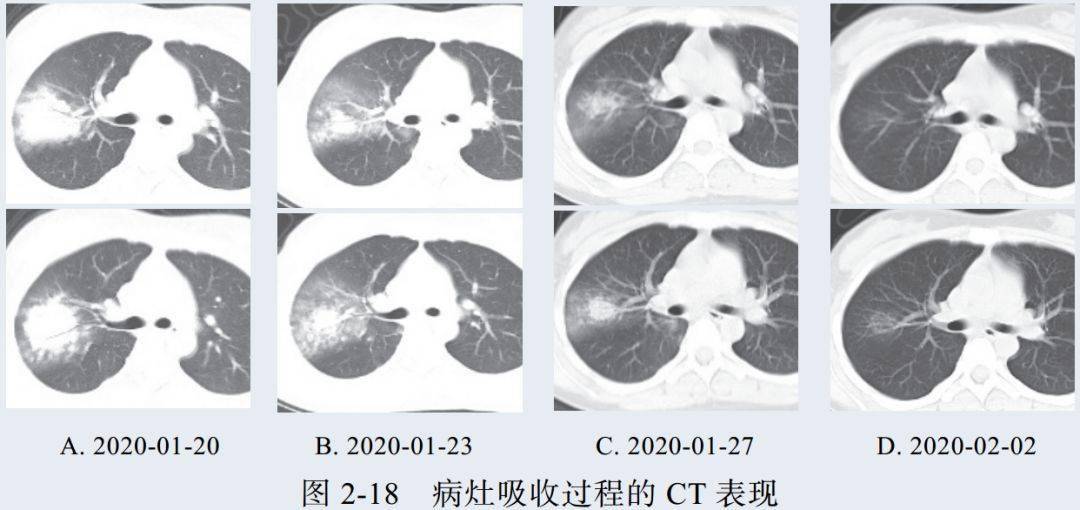

四、消散期征象

多数病例在 14 天后进入病灶消散期,表现为病灶逐步吸收,可遗留少许条索状高密度影,提示纤维化。少部分病例病程较短,影像可由早期表现直接进入消散期(图 2-17)

病例展示

4. 消散期片状 GGO 可完全吸收,肺内病灶向纤维化演变